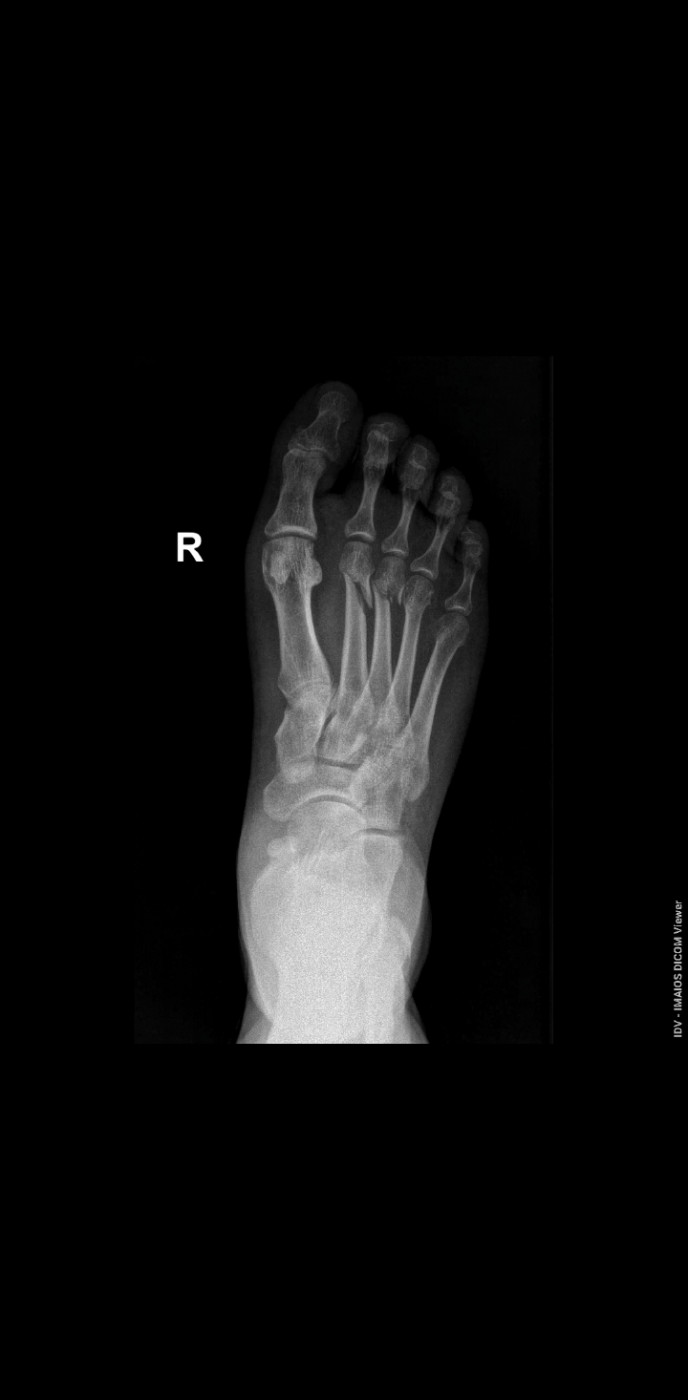

Нужна ли операция?   1 ответ

Здравствуйте доктор! Подскажите, пожалуйста, нужна ли операция при таком переломе? Или достаточно гипса? Почему то не получается загрузить второй снимок.